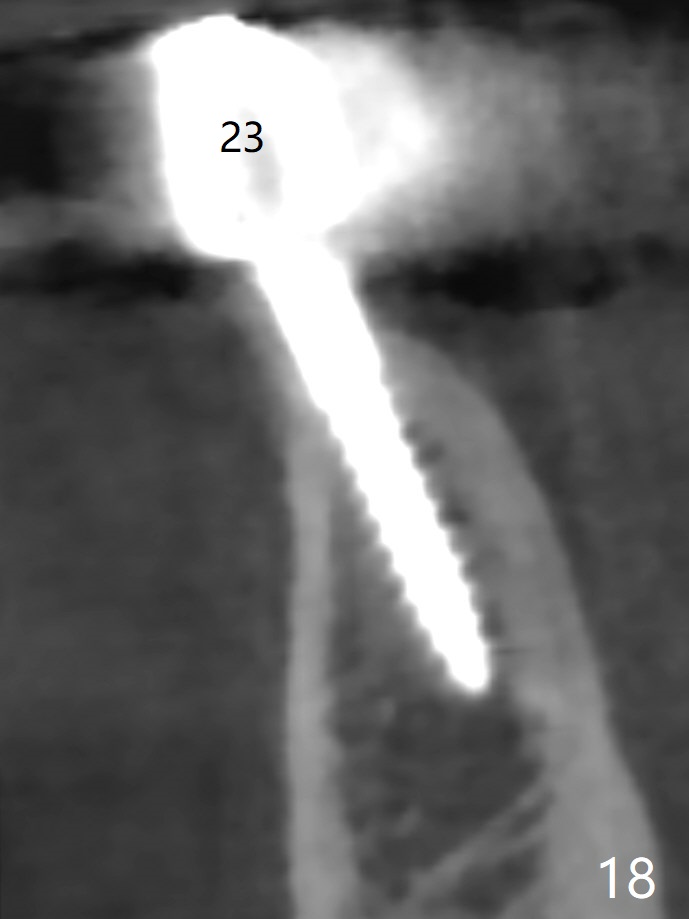

The mesial defect at #27 appears to have been repaired 8 months postop (Fig.8,9 *); there is no bone loss at 1-piece implant sites. The gingival recession seems to remain the same before and after removal of the provisional FPD (Fig.10,11). The bulging abutment at the cervix is less prominent when a straight abutment is used and prepared (Fig.12, 4.5x5.5(5) mm). There is no bone loss at #23, 25 and 27 sites 2.5 years post cementation (Fig.12-15), although the trajectory of the implants could be improved by using surgical guide (Fig.16-18).